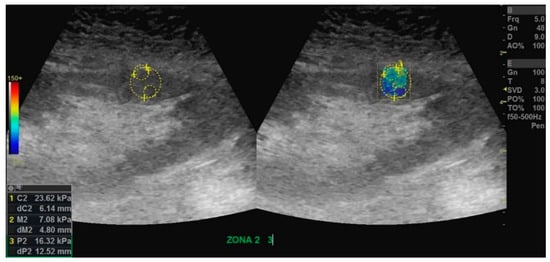

2.4. Shear Wave Elastography Examination